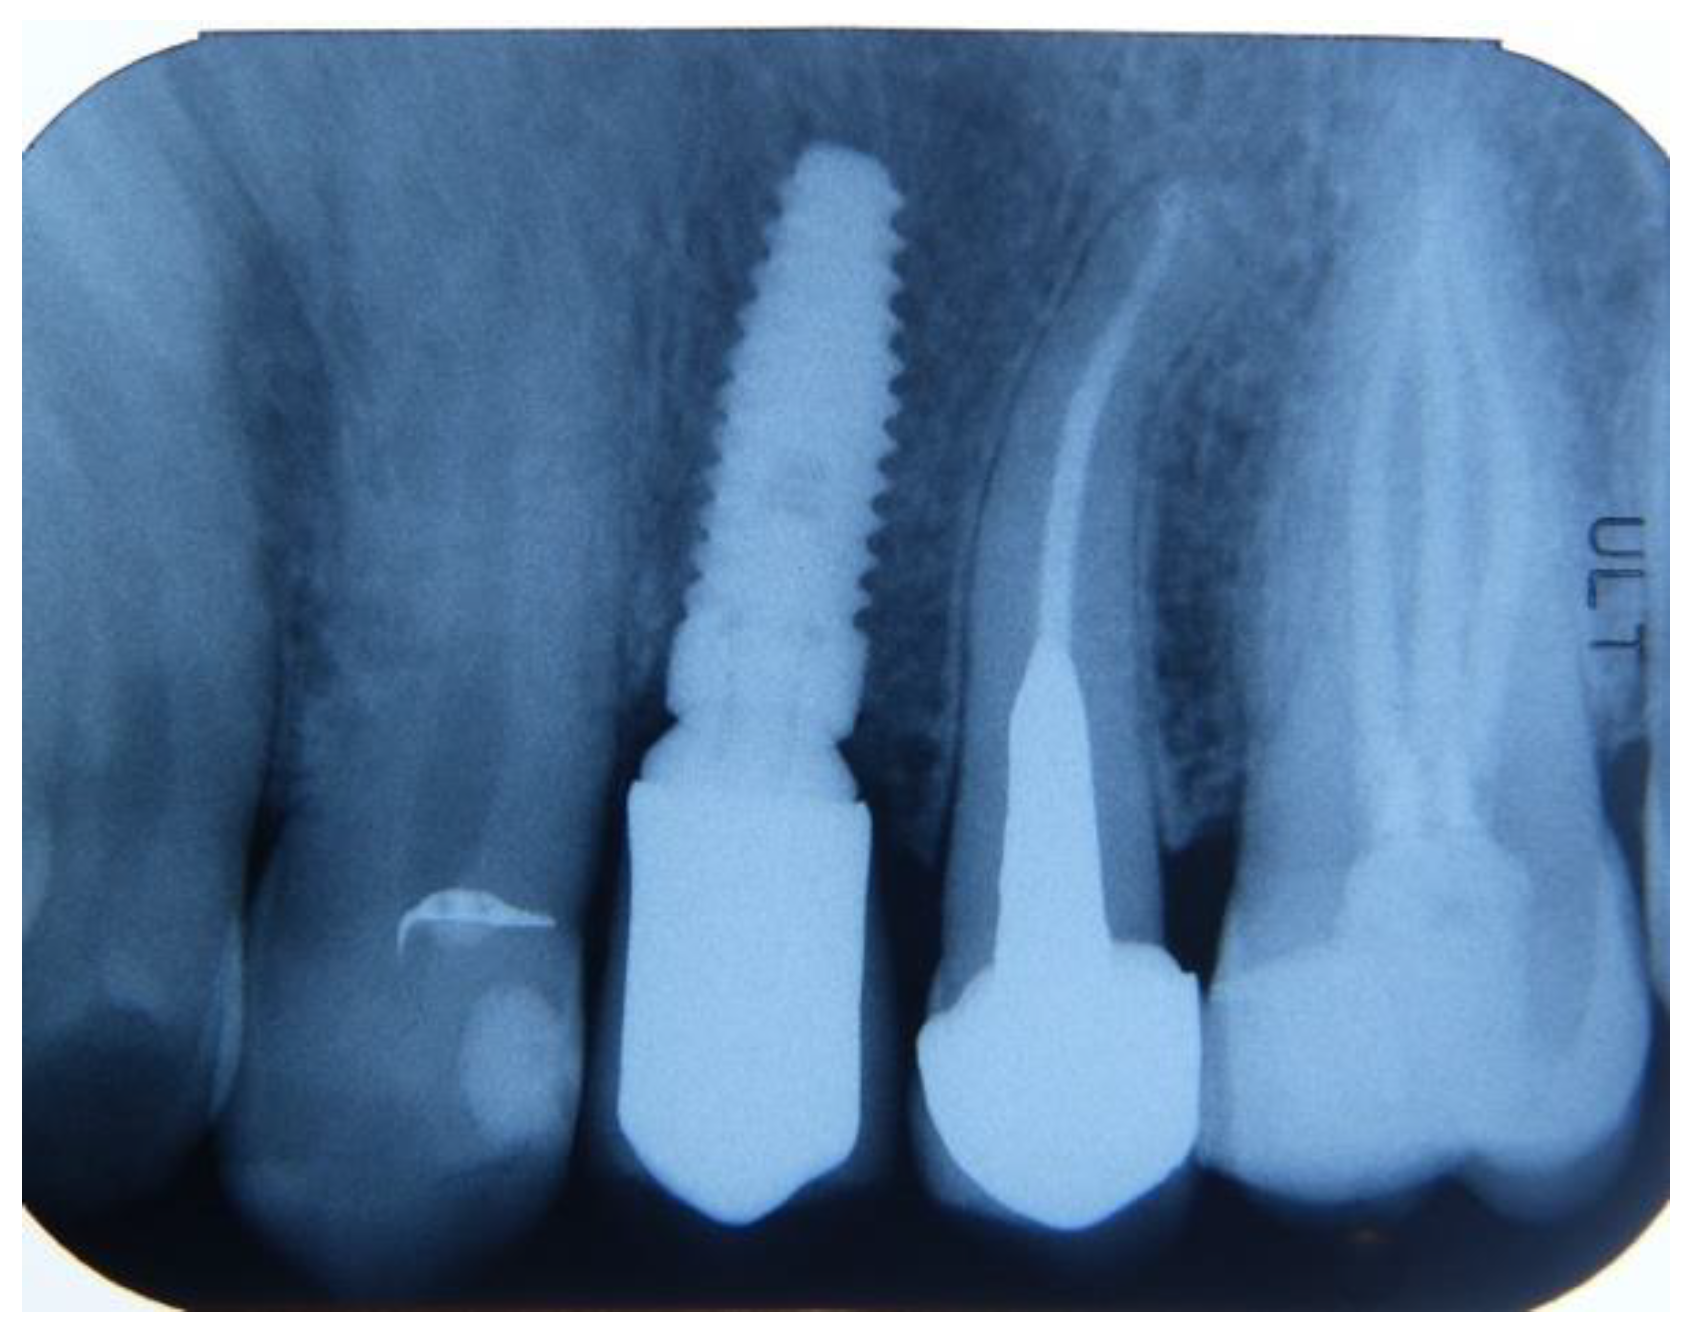

- Subjects who underwent surgical intervention for tooth removal and alveolar socket preservation using exclusively a tooth-derived bone substitute (Tooth Transformer®—Tooth Transformer SRL).

2.3. Preoperative and Surgical Procedures